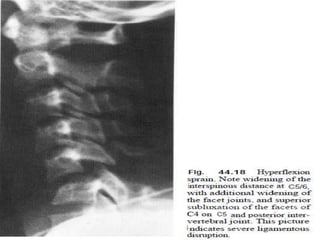

Classification of Hangman' s fractures

Type II (28%)

 disrupted C2-3 disc

instability

fracture

 displaced C2

 Severe instability

HANGMAN FRACTURE

TYPE 3

Prevertebral soft

tissue swelling

Anterior

dislocation of the

C2 vertebral body

BILATRAL C2 pars

interarticularis

fractures.



The CT-images

confirm the

fracture-lines of

the hangman's

fracture.

They run

through the

pars

resulting in a

traumatic

spondylolysis.

In this case